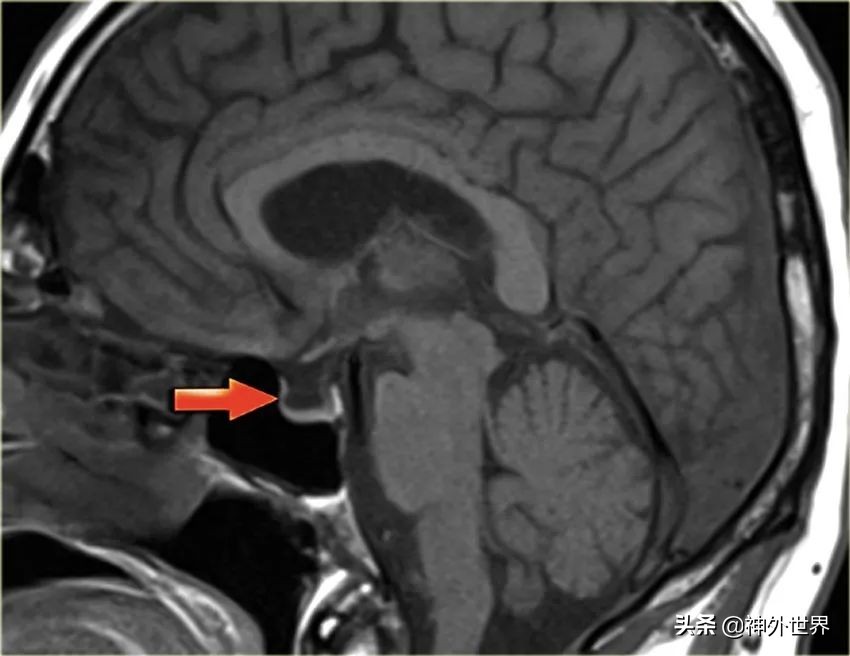

- 垂体发育障碍:漏斗未能向下发育至鞍内,垂体柄消失,神经垂体上移。

- Rathke囊肿:鞍区囊性病变【Rathke囊发育退化不全】。